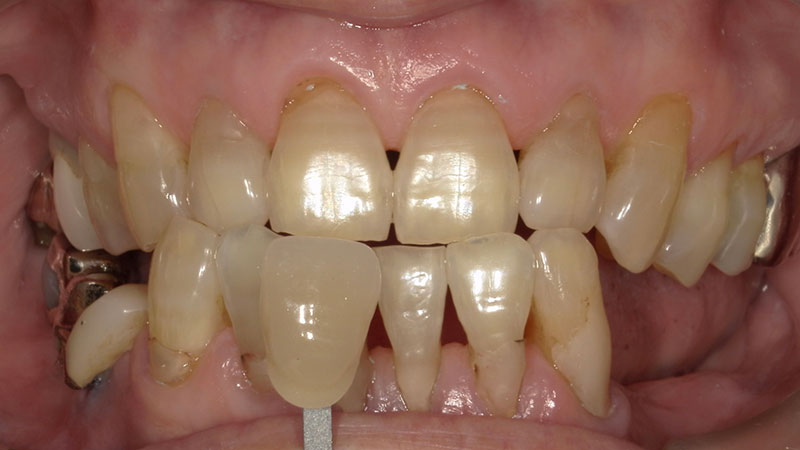

ホワイトニング

デュアルホワイトニング症例

デュアルホワイトニング症例をご紹介します。

ホワイトニングにはオフィスホワイトニングとホームホワイトニングに分けられます。

オフィスホワイトニングは医療ホワイトニングの一つで歯科医院に来院で施術を受けます。

ホームホワイトニングは専用のマウスピースに薬剤を入れて1日数時間はめるものになります。

デュアルホワイトニングとはオフィスとホームを併用する処置になります。

オフィスのいいところである短時間での漂白と、ホームのいいところである持続的な漂白が可能になります。

今回のように加齢で黄ばんだ頑固な着色も真っ白にできます。

デメリットとして2種類するので手間がかかります。

加齢による歯の黄ばみはクリーニングだけでは綺麗になりません。

また、今回のように歯にまだら模様の変色がある場合はホワイトニングによって目立たなくなります。

今回させていただいたオフィスホワイトニングは1ヶ月集中コースになります。

1ヶ月間通い放題(中2日空ける)の平日のみのお得なコースです。

短期間で一気に白くしたい方、平日に通いやすい方に向いているコースになります。

| 患者様 | 70代女性 |

|---|---|

| 主訴 | 全体的な黄ばみが気になる |

| 治療費 | ベーシックコース77,000円(税込) ホームホワイトニング16,500円(税込) 総額93,500円(税込) |

| 治療期間 | オフィスホワイトニング8回 ホームホワイトニング1ヶ月 |